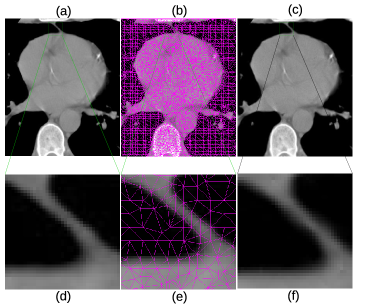

In Fig. 4, more details of the Lena experiment are shown. (a) is the original Lena image, the same as Fig. 3 (a). (b) is the mesh generated by the method outlined in section 2.1. (c) is the recovered image, which is the same as Fig. 3 (e). To visually see the generated mesh and compare the difference between the original and restored images, Fig. 4 (d)–(f) are the zoomed-in views of (a)–(c), respectively. As the results show, the mesh quality is high enough for subsequent numerical analysis and the the recovered image is very close to the original one. As a matter of fact, the restored image looks smoother due to the smooth radial basis functions used, and the sharp edge features are well preserved. Fig. 5 shows the original brain MRI, its generated mesh, and the result of ARBF interpolation using intensities on triangle centers with the MQ basis function. The zoomed-in views show the quality of mesh and restoration as well. Fig. 6 shows another MRI experiment of breast. Fig. 7 shows a CT-scanning experiment. From all these examples, one can see the effectiveness of the proposed approaches for image mesh generation and feature-preserving restoration.

Figure 7: Details of CT-scanned image of heart. (a) Original heart image. (b) Generated mesh of (a). (c) Result of triangle-based ARBF interpolation using MQ basis. (d)–(f) are zoomed-in views of (a)–(c), respectively.

Breast 512×512512512512\times 512 5% 11.8763 0.5 8.70